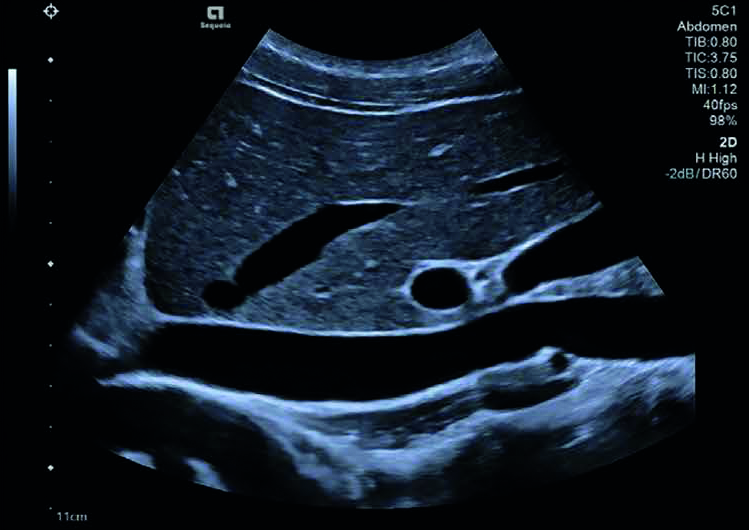

Imaging completamente focalizzato del fegato e IVC utilizzando la tecnologia Infocus che offre uniformità dell’immagine in tutto il campo visivo.